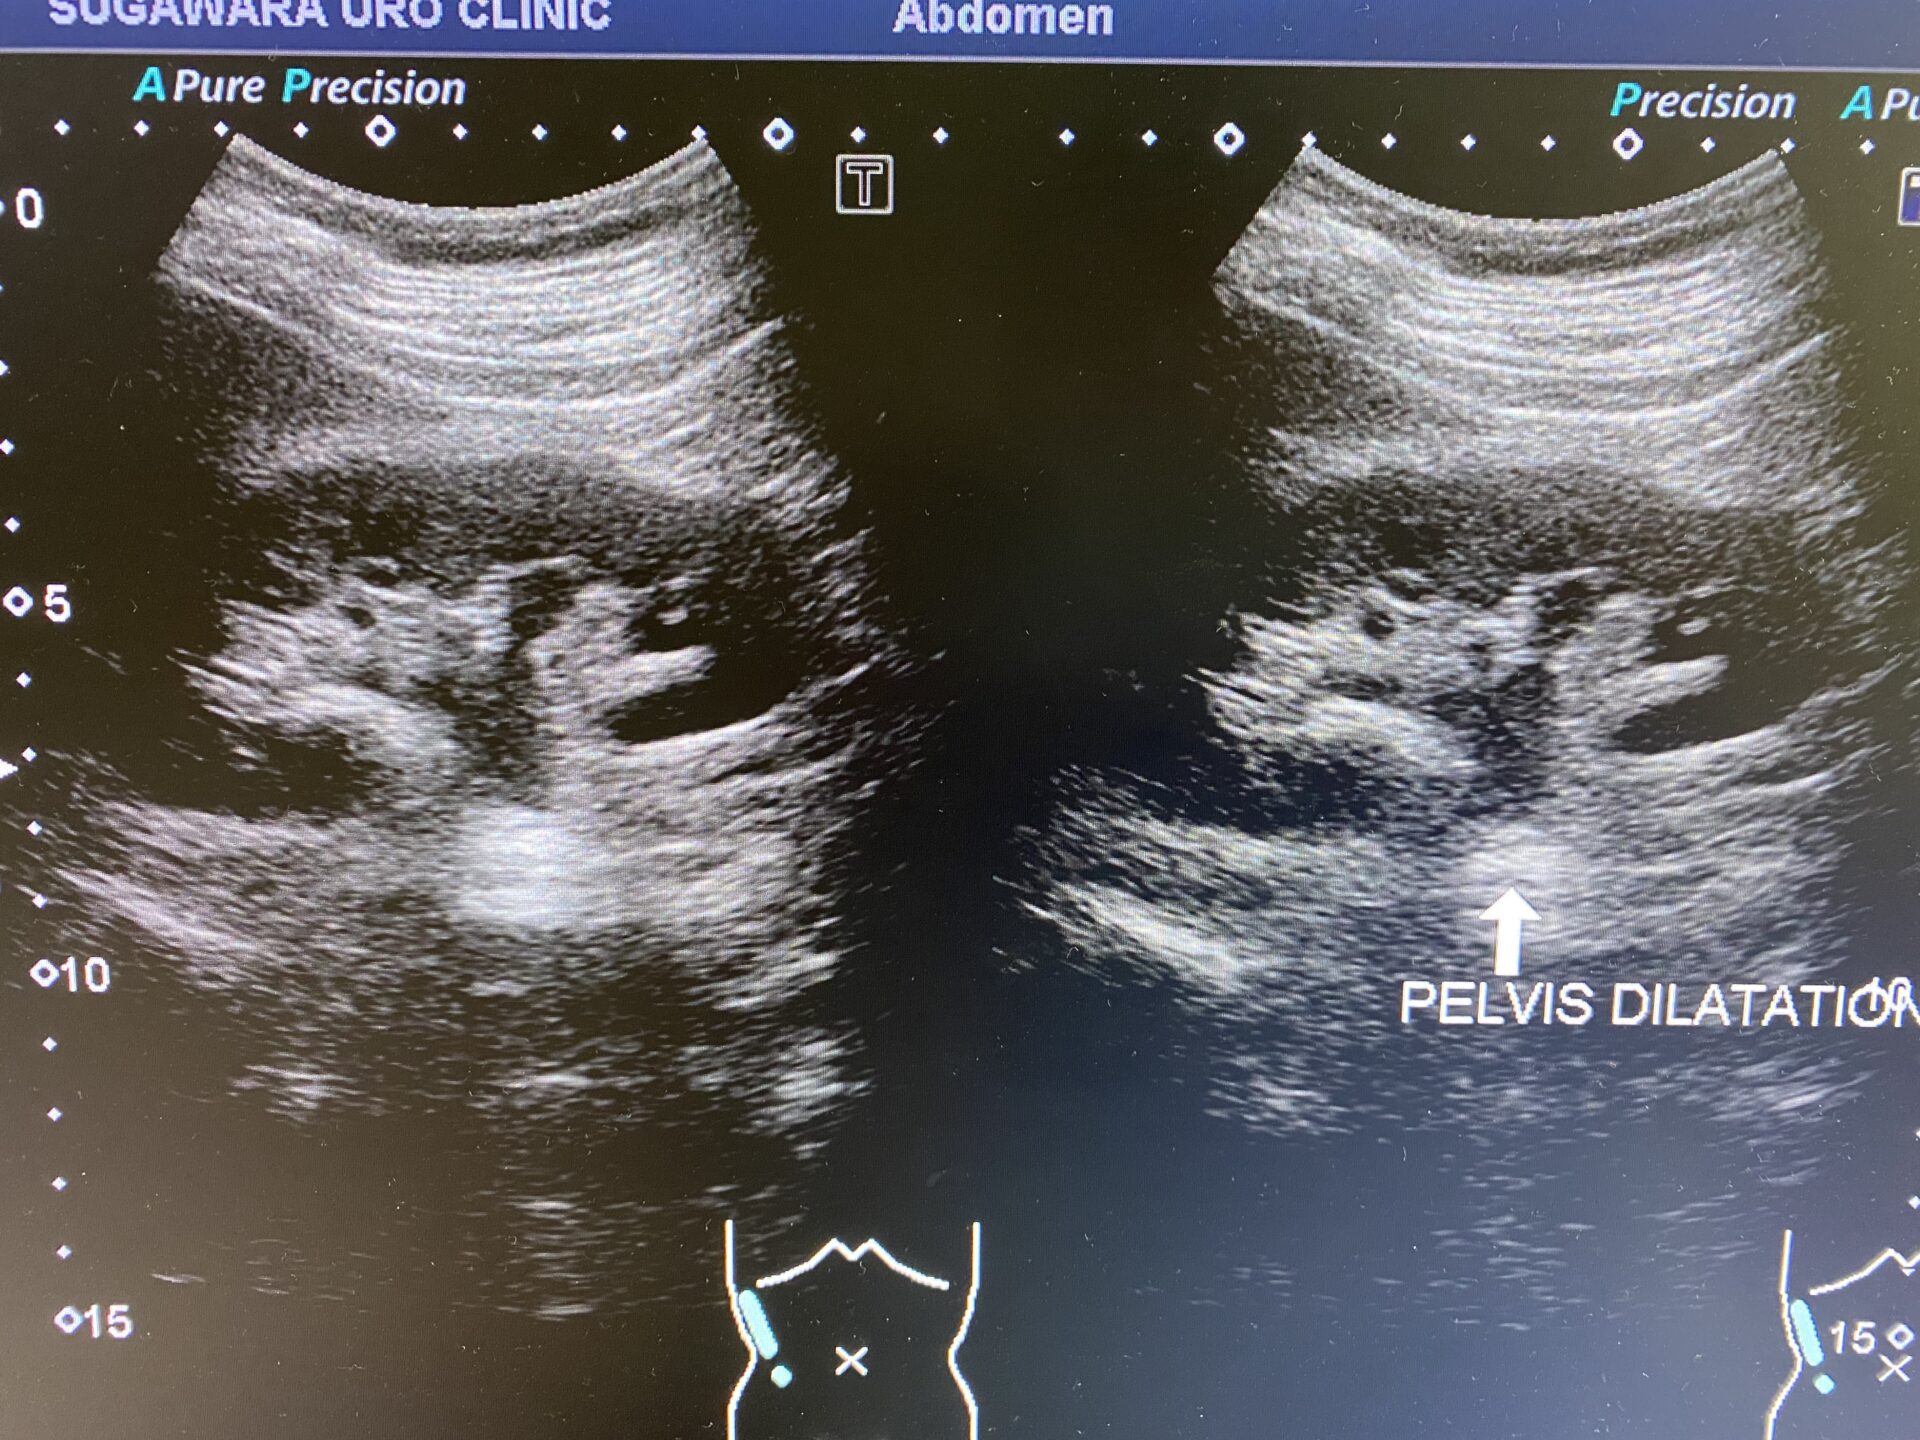

今回の方は尿路エコー上左腎に大きな結石を認め、右腎盂は拡張しておりました。また、右尿管下端(膀胱尿管移行部)に結石が存在し、ここが尿の通過障害となっており、右腎盂拡張の原因となっていたようです。(今回は腎杯の拡張までに至っておりませんので、厳密にはいわゆる水腎症という診断にはなりませんでした)